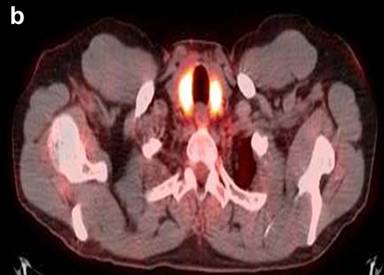

A 53-year-old white male, nonsmoker, was self-referred to our clinic for an enlarged prostate. Past medical history was significant for “idiopathic” pancreatitis (10 years ago), which resulted in diabetes mellitus type 2, benign prostate hypertrophy (for 4 years), asthma, and hypothyroidism. He complained of having a weak urine stream for 4 months. Prior to coming to our institution, the patient had a biopsy of the hard palate secondary to soft tissue inflammation; immunostaining was positive for IgG4 cells. Hence, systemic IgG4-related sclerosing disease was suspected. PET/CT, which was performed at our center, showed a diffuse tracer uptake by the prostate (Figure 5). In addition, it also revealed several hypermetabolic lesions in the salivary glands, thyroid (Figure 6), both bronchi, right hilar lymph nodes, right middle lung lobe (Figure 7), pancreas (Figure 8), and left kidney (Figure 9). PET/CT images were consistent with systemic IgG4-related sclerosing disease. Also, immunostaining of the prostate at our institution demonstrated a high number of IgG4-positive cells in high power field (Figure 10). IgG level was high (2,260 mg/dL); IgG4 level was not obtained. IgE was elevated (IgE: 1,125 KU/L). Prostate-specific antigen was normal (0.13 ng/mL; reference range: 0-4.00 ng/mL). Prednisone 40 mg daily was initiated and benign prostate hypertrophy symptoms resolved after one month of treatment. A two-month follow-up PET/CT showed resolution (Figure 11). Currently, the patient has been tapering off the prednisone and is asymptomatic.

Figure 5. Composite PET/CT images show an intense tracer uptake by the prostate. Case#2. |